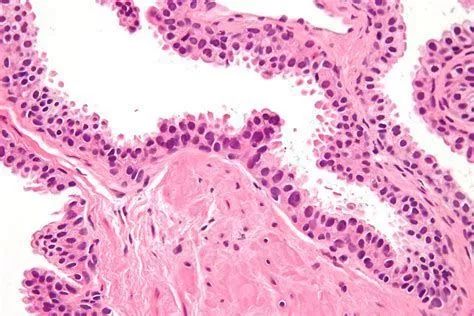

乳腺癌可以根据某些特殊的模式转移到其他器官,这是一项由瑞典卡罗林斯卡研究所、瑞典皇家理工学院(KTH)和芬兰赫尔辛基大学的研究人员发现的,他们通过研究癌细胞DNA对病人乳腺癌的转移途径进行了总结。相关研究成果于近日发表在《Journal of Clinical Investigation》上。

腋窝淋巴结中的转移灶是乳腺癌转移至其他器官的重要风险因素。此前未知的是是否这些转移灶进一步将癌症转移至其他器官以及癌细胞采用哪种途径转移。

在这项新研究中,研究人员研究了20个病人的乳腺癌组织、腋窝淋巴结及其他器官的转移灶中癌组织的DNA。通过一种叫做下一代测序的新技术,研究人员绘制了乳腺中的癌细胞和其他器官的转移灶的关系。这使他们找到了癌症转移的途径。

这项研究表明癌细胞从乳腺癌组织中转移到腋窝淋巴结以及其他器官。下一步的转移灶通常从这些器官中转移。

“我们最重要的发现是腋窝淋巴结的转移灶似乎并不会进一步转移到其他器官,因此尽管这些转移灶可以展现出癌症的恶性程度,但是并不是它们引起了转移。” Johan Hartman说道。他是卡罗林斯卡研究所肿瘤病理系副教授,也是该研究的领导者之一。

他们还发现某些情况下乳腺癌中的癌细胞会同时在不同的器官形成转移灶。研究人员还揭示了乳腺癌的不同区域会引起身体特定的组织形成转移灶。